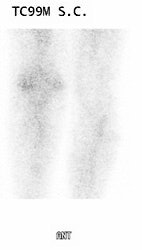

|

Infected knee prosthesis: The patient had a history of an infected right knee prosthesis. Combined In-111 WBC and Tc-sulfur colloid marrow imaging was performed to evaluate for residual infection following treatment prior to re-do knee replacement. The white blood cell exam demonstrated incongruent WBC accumulation along the mid portion of the right knee joint (black arrow) consistent with unresolved infection. |